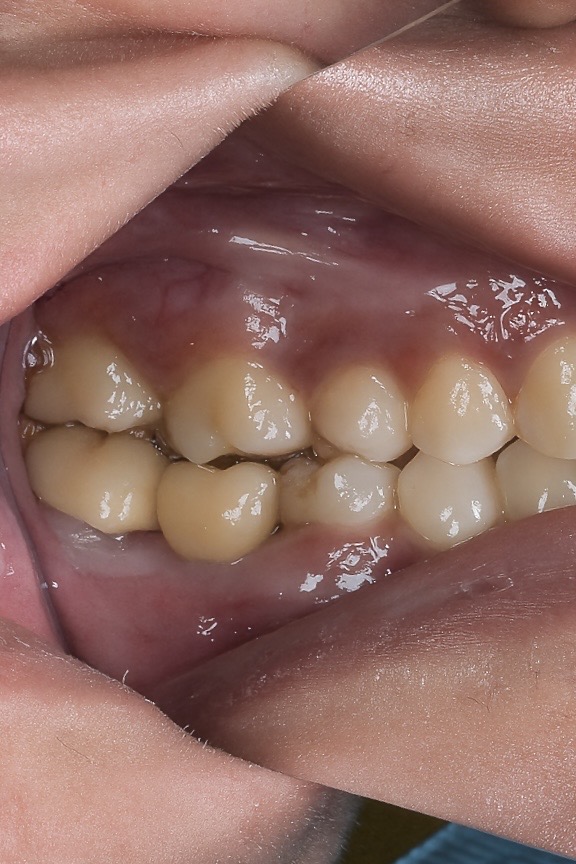

4️⃣ Prosthetic Phase

A digital scan using an intraoral scanner captured the implant position. A titanium base with CAD-CAM zirconia screw-retained crown was fabricated. The screw-channel was positioned lingually for optimal esthetics and retrievability (Fig 3 & 4).